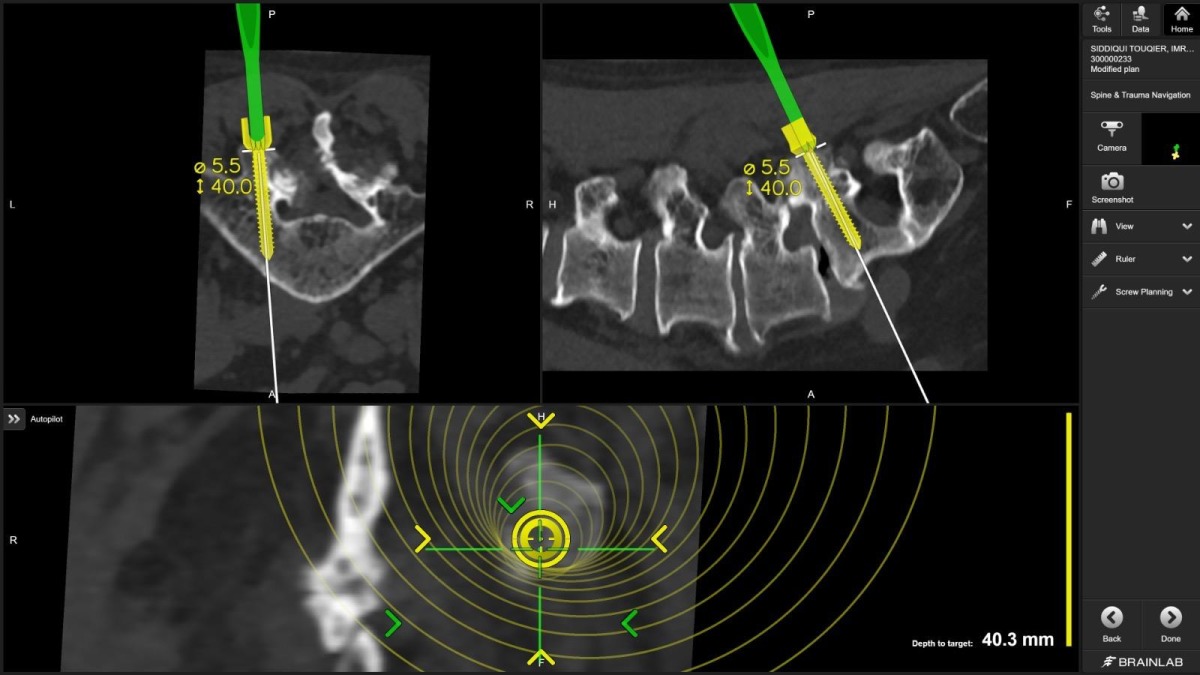

"For the first time in Qatar, I used virtual reality technology to plan spine screws before surgery," Dr. Belkhair explains. "These electronic glasses showed me 3D images of the patient's CT scan, allowing me to plan screw placement in the perfect position. What I saw in those glasses translated directly into the operating room, visible on screens, guiding every movement."

Dr. Belkhair took this further. Before the patient entered the operating room, he used virtual reality glasses that transformed CT scan data into an immersive, three-dimensional surgical rehearsal space. He could rotate the spine, zoom into pedicles (the narrow bone corridors where screws must pass), measure angles, and plan screw trajectories with unprecedented detail.

"The planning became the roadmap. The navigation ensured we followed it perfectly," he notes.

Dr. Belkhair's integration of VR planning with intraoperative navigation creates a seamless workflow: plan in virtual space, execute with real-time guidance, verify with immediate imaging.

"The glasses showed me the patient's spine as if I could hold it in my hands," Dr. Belkhair describes. "I could see where every screw needed to go, what angle, what depth. It's surgical precision at a level we couldn't achieve even five years ago."